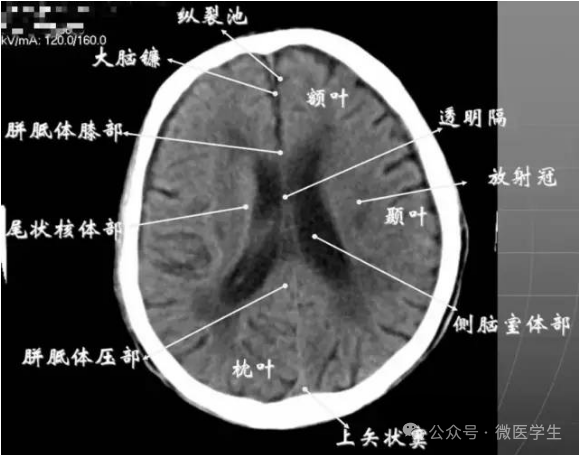

由额、颞、枕叶构成,两侧侧脑室体部之间为透明隔,外侧为尾状核和体部。侧脑室后角(枕角)可不对称,室内可见脉络丛钙化。中线处可见大脑纵裂池和大脑镰。

内侧壁侧脑室体部被胼胝体分开,侧脑室体部的外方为顶叶,顶枕沟及中央沟将大脑为为额、顶、枕叶。

- 放射冠:是内囊到大脑皮质间的放射状纤维白质。